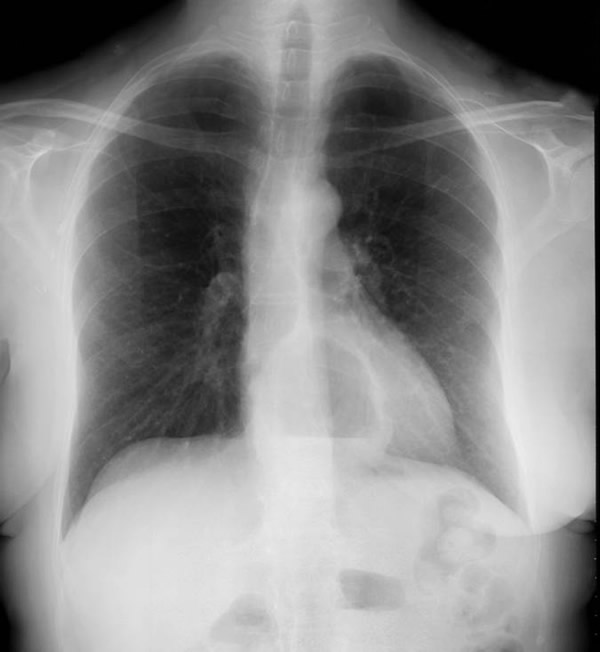

The clinical manifestations are unpredictable and are not influenced by the size of the diverticulum but rather correlate with the underlying motility disturbance. Dysphagia and regurgitation are the predominant symptoms observed. Respiratory complaints, when present, indicate aspiration. Most esophageal diverticuli are found incidentally. Chest radiography may be normal or may reveal a mediastinal density or air-fluid level (Figure 1). This feature may be misdiagnosed as a hiatus hernia. The diagnosis of an epiphrenic diverticulum is usually made on an upper gastrointestinal series (Figure 2). Oblique views can define the size, location, number and shape of diverticula. Contrast studies, however, are unreliable for evaluating motility patterns and thus esophageal manometry should be performed preoperatively. Correct placement of the catheter can be difficult and may be assisted with endoscopic guidance. Esophageal endoscopy is recommended to exclude other etiologies for dysphagia. This maneuver can be difficult and should be performed by an experienced endoscopist.